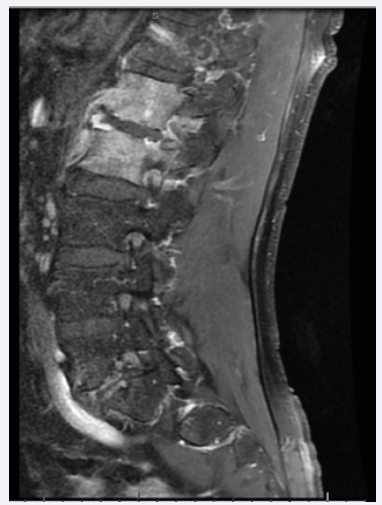

After six weeks without improvement with regular physical therapy, his exam remained unchanged, and an MRI was obtained(Figure 1).

Figure 1 Sagittal T1-weighted Contrast MRI of Lumbar Spine showing abnormal signal enhancement at L1 and L2.

It showed multiple areas of abnormal enhancement involving cancellous portions of L1 and L2, with extension into the adjacent paraspinal musculature. Laboratory studies were unremarkable except for mild normocytic anemia with a hemoglobin of 11.2 mg/CL, and elevated ESR and CRP levels, at 65 mm/hr and 16.1 mg/L, respectively. An urgent biopsy under fluoroscopy was obtained. After the biopsy, the patient was admitted to the inpatient medicine service for pain control and management of presumed vertebral osteomyelitis. His physical examination revealed normal vital signs and a normal exam except for lumbar spine and paraspinal pain with palpation. He was treated with broad-spectrum antibiotics (vancomycin and ceftriaxone) and parenteral opioids for pain control. On the fourth day after the patient’s biopsy, his tissue cultures grew out Eikenella corrodens.